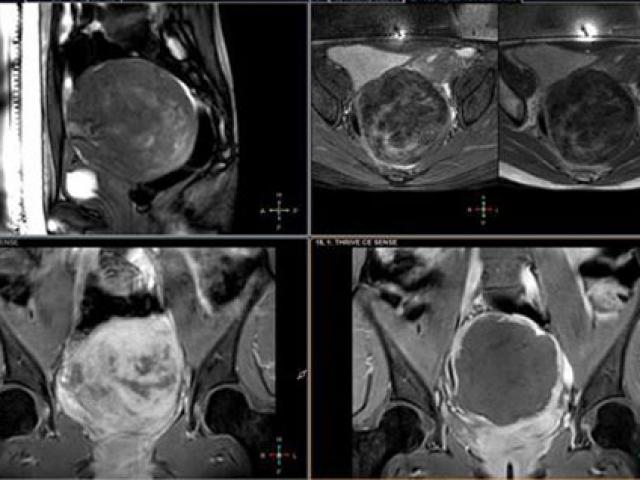

Kinh nguyệt có màu trong như nước, hoàn toàn không có màu đỏ hoặc đỏ nhạt chứng tỏ bạn cơ thể đang thiếu dưỡng chất trầm trọng, thậm chí bạn có thể đối mặt với nguy cơ ung thư buồng trứng. Tuy nhiên, bệnh ung thư này rất hiếm gặp, chỉ chiếm 1-2% trong tất cả các bệnh phụ khoa.